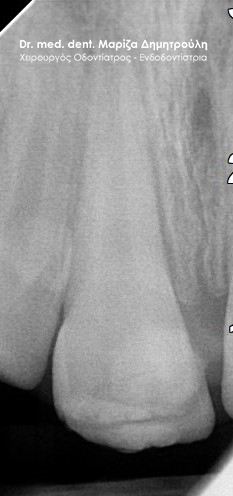

Root canal treatment

BEFORE